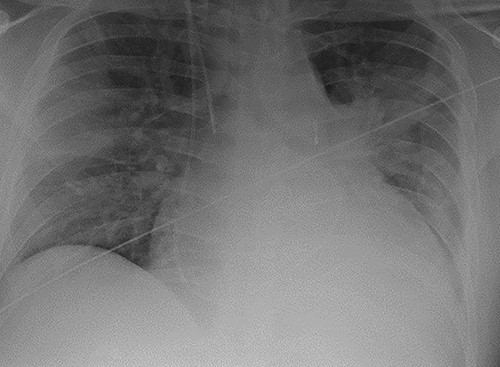

A 38-year-old Caucasian male presented to hospital with shortness of breath. He was diagnosed with dilated cardiomyopathy following transthoracic echocardiography. He continued to deteriorate and developed florid pulmonary oedema as demonstrated in Fig. 1, necessitating his transfer to our centre for further management. Prior to this presentation he had no known comorbidities.

Chest radiograph demonstrating pulmonary oedema prior to implantation of biventricular assist device.